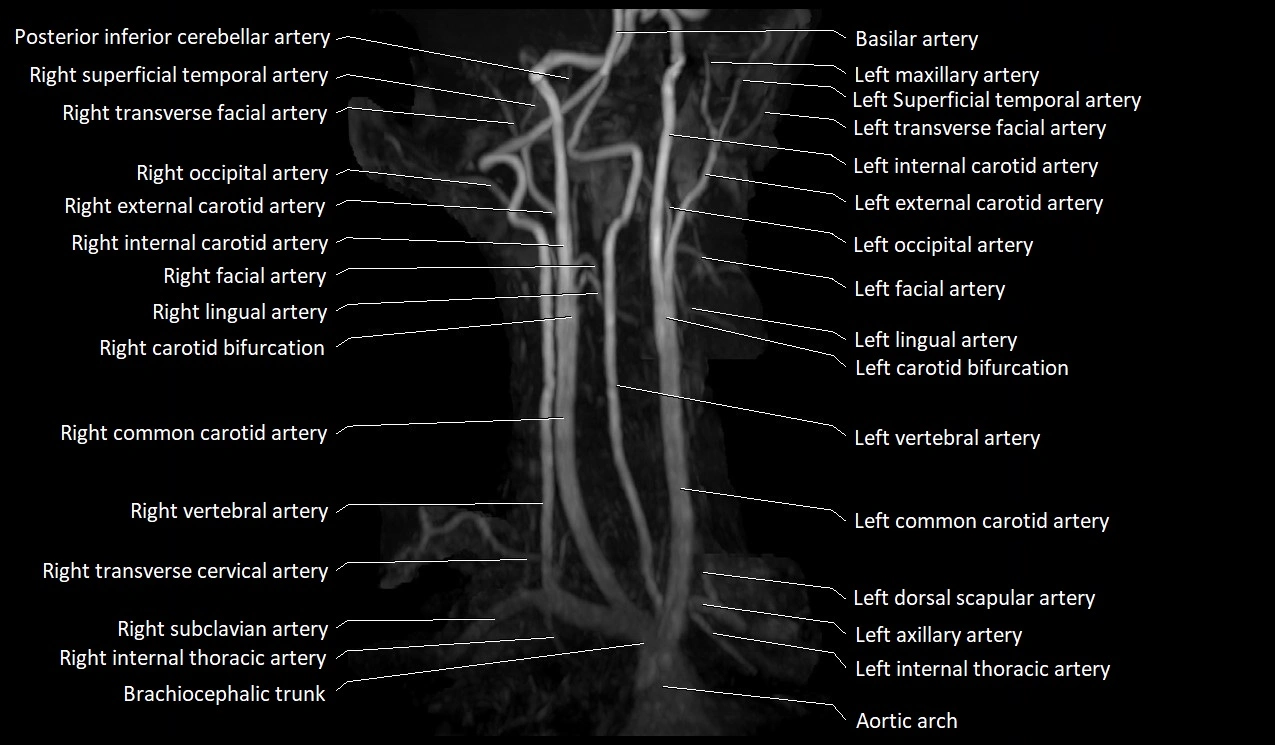

CT image

image